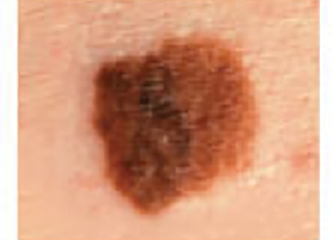

Melanoma Photos

Nodular melanoma on the leg of a Native American woman.

Photo: International Skin Imaging Collaboration

Amelanotic melanomas may be pinkish-looking, reddish, purple, normal skin color or essentially clear and colorless.